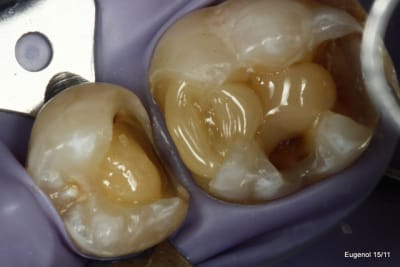

SC12 (35) SC17 (36) sc7 + sc7 (37), 50mn ...

maquillant Enamel HFO

Sinon je fais les sillons secondaire a la sonde.

C'est du compo Enamel HRI en dentine et Esthelite en email qui se sculpte facilement et reste pourtant souple et autolissant...

Le polissage c'est des brossettes chargées en silice, et avec de la pâte à polir.